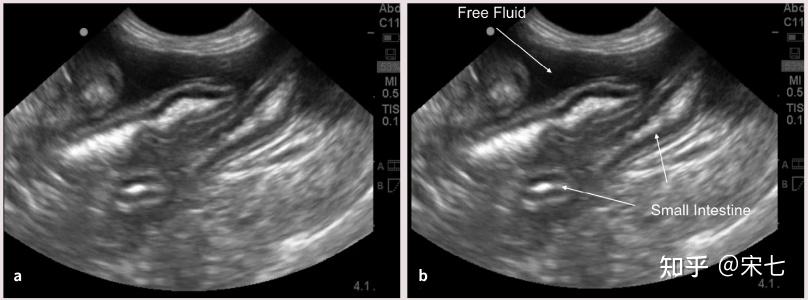

猫传腹(fip)的影像诊断

图片尺寸808x300